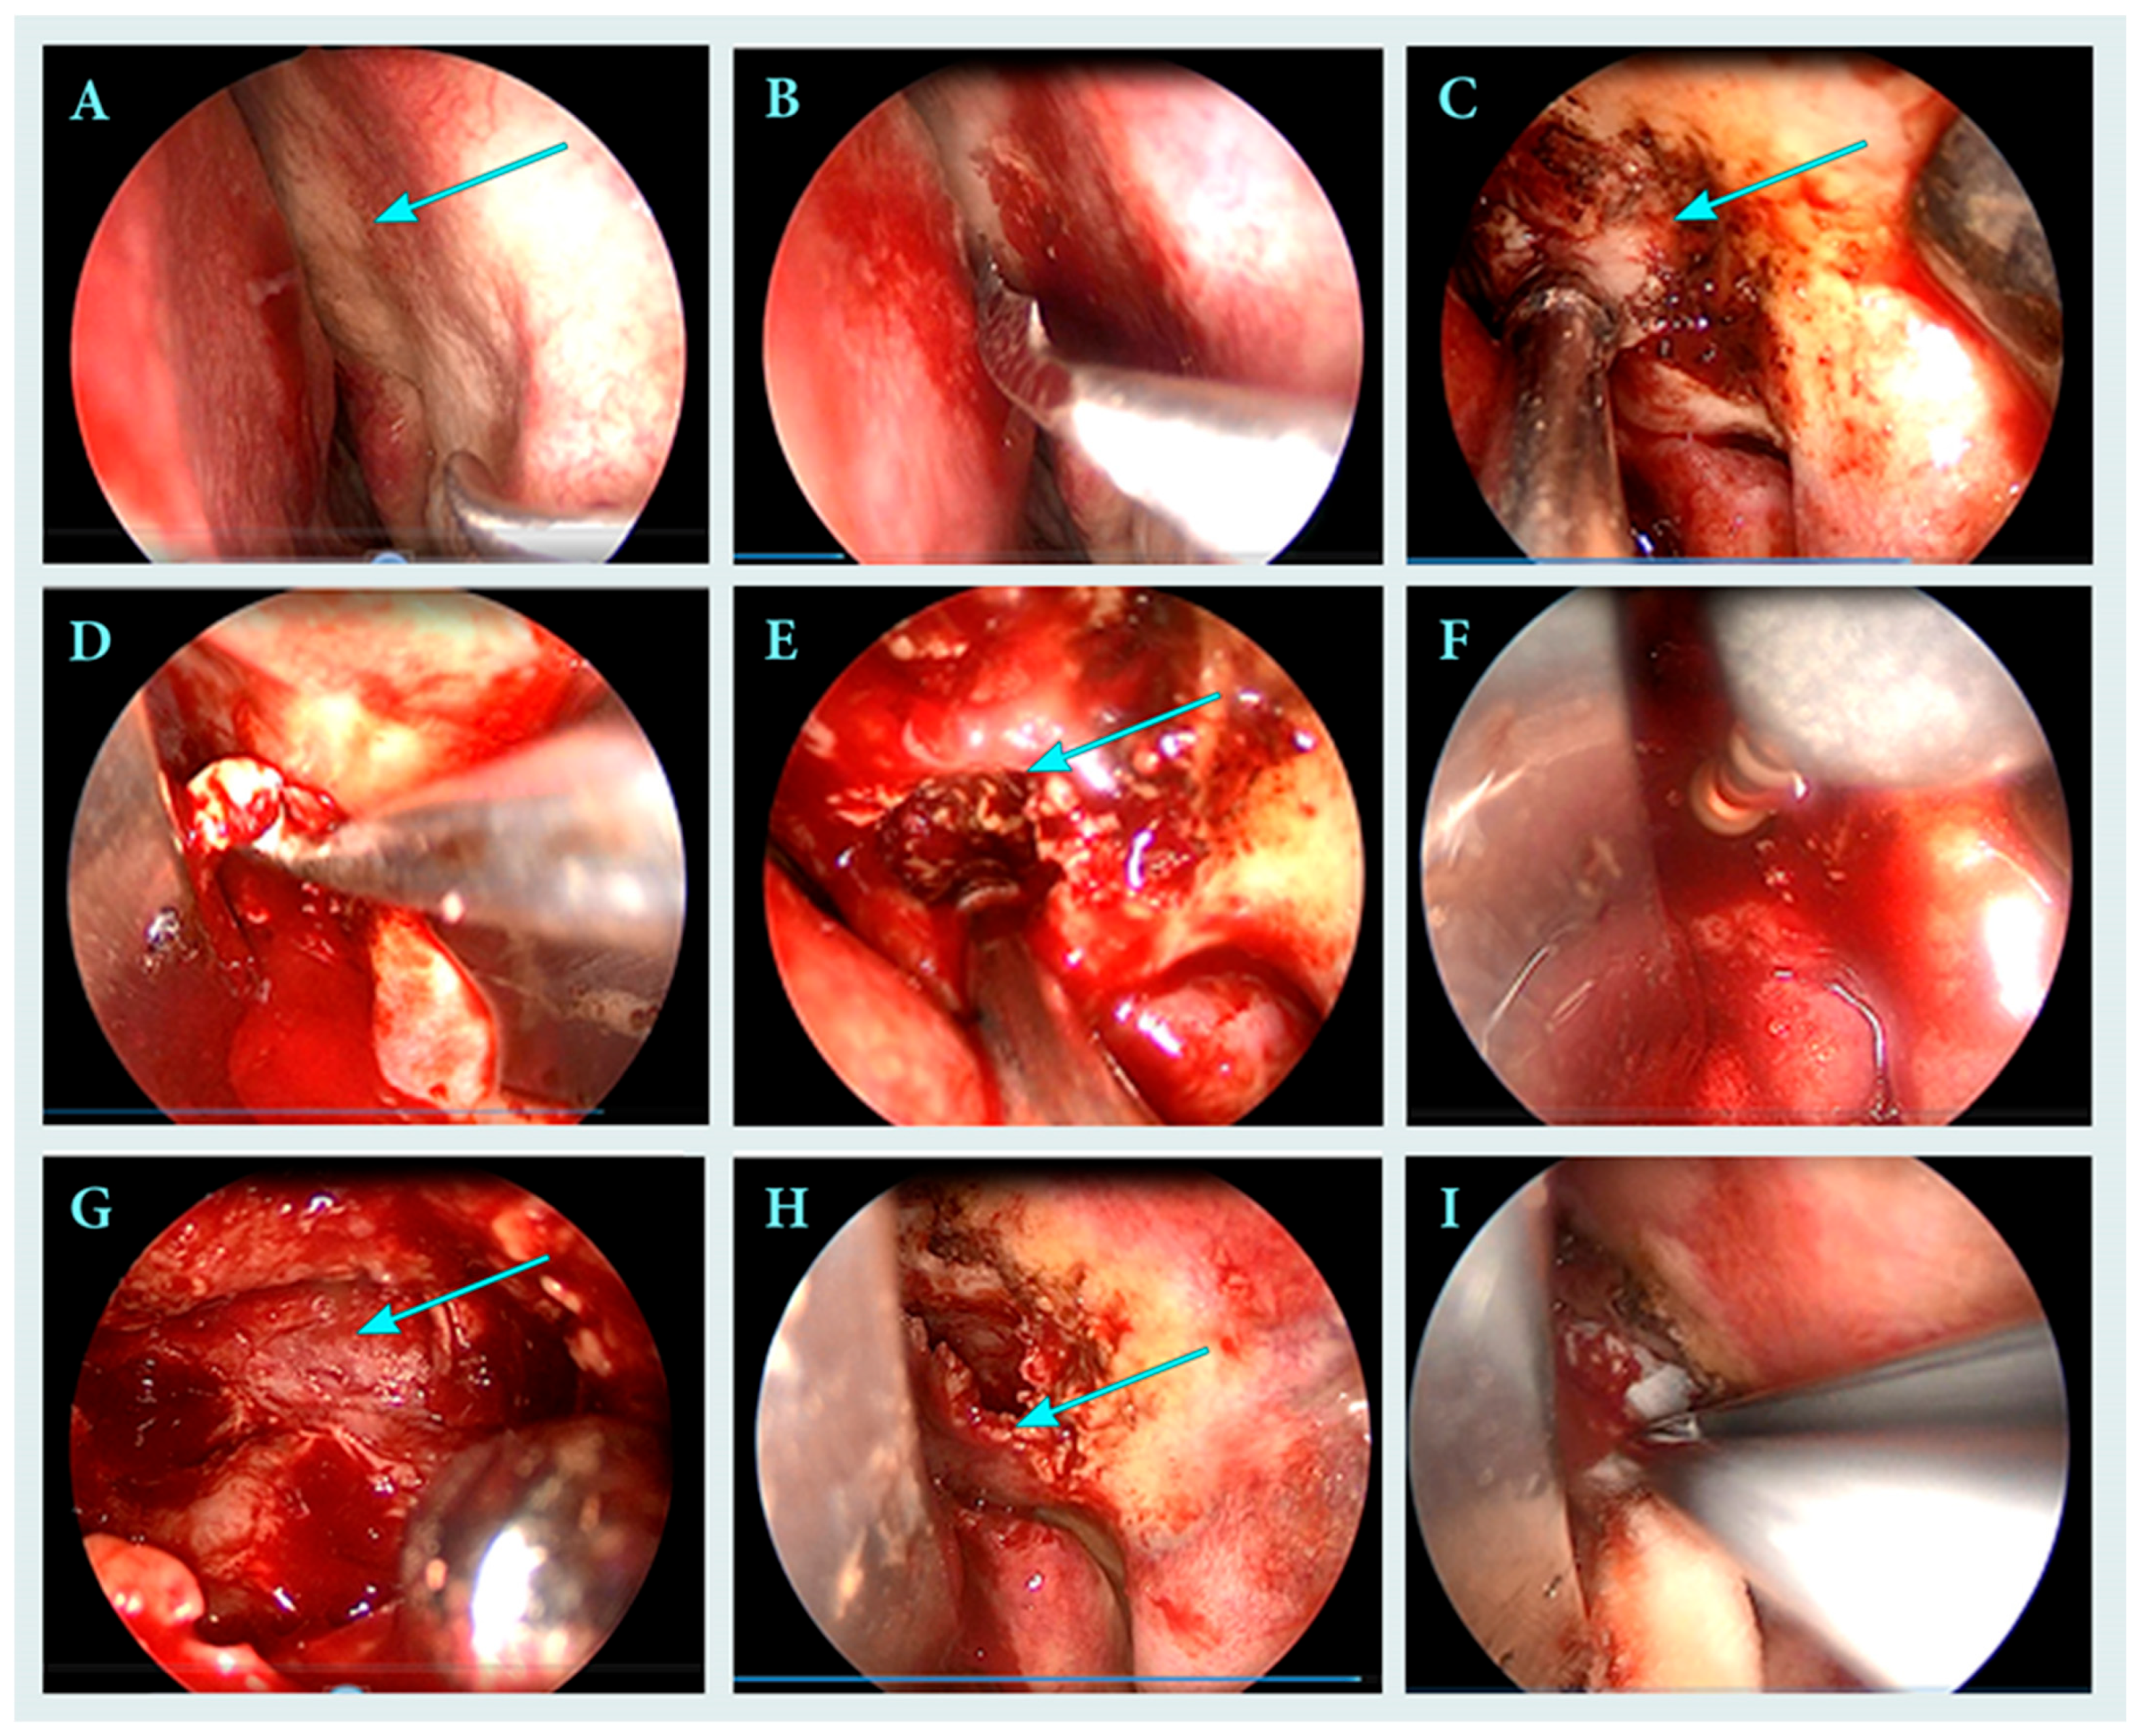

2.2. Surgical Treatment